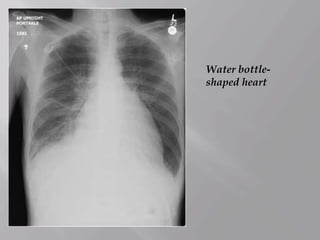

Water bottle-

shaped heart

This image is from a patient with malignant pericardial effusion. Note

the "water-bottle" appearance of the cardiac silhouette in the

anteroposterior (AP) chest film.